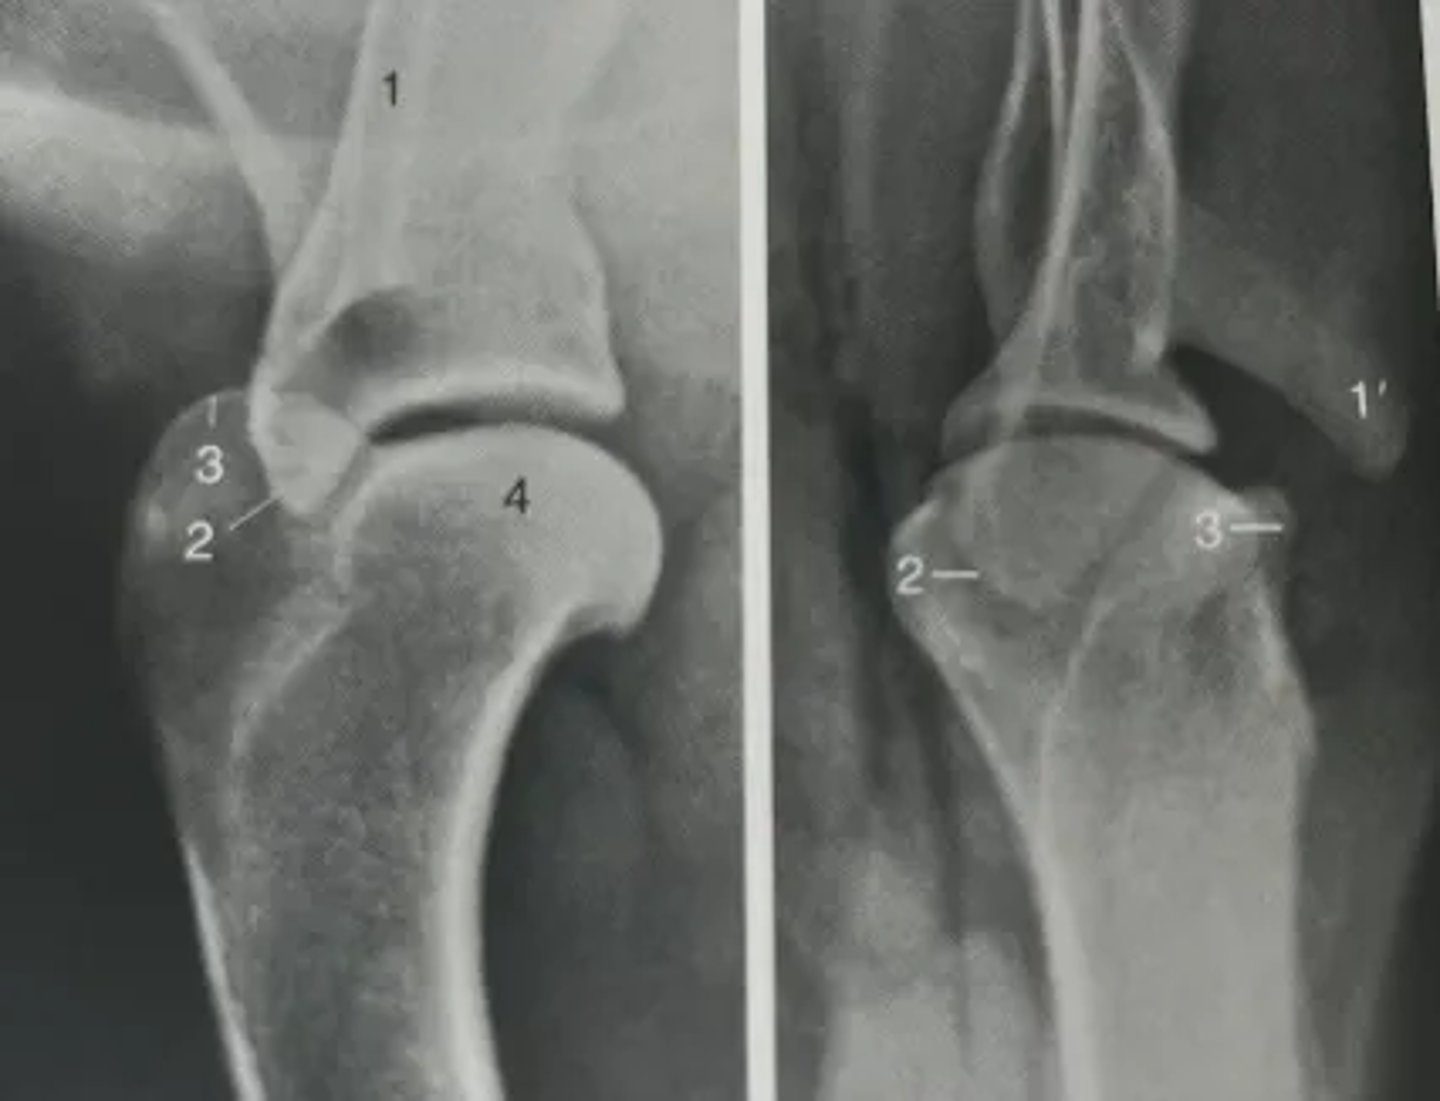

Identify features of the shoulder on a radiograph.

1. Spine of scapula

1'. Acromion

2. Supraglenoid tubercle

3. Greater tubercle of humerus

4. Head of humerus

Identify features of the elbow on a radiograph.

1. Humerus

1'. Medial epicondyle

2. Radius

3. Ulna

3'. Olecranon

3''. Apophysis of tuber olecrani

4. Anconeal process